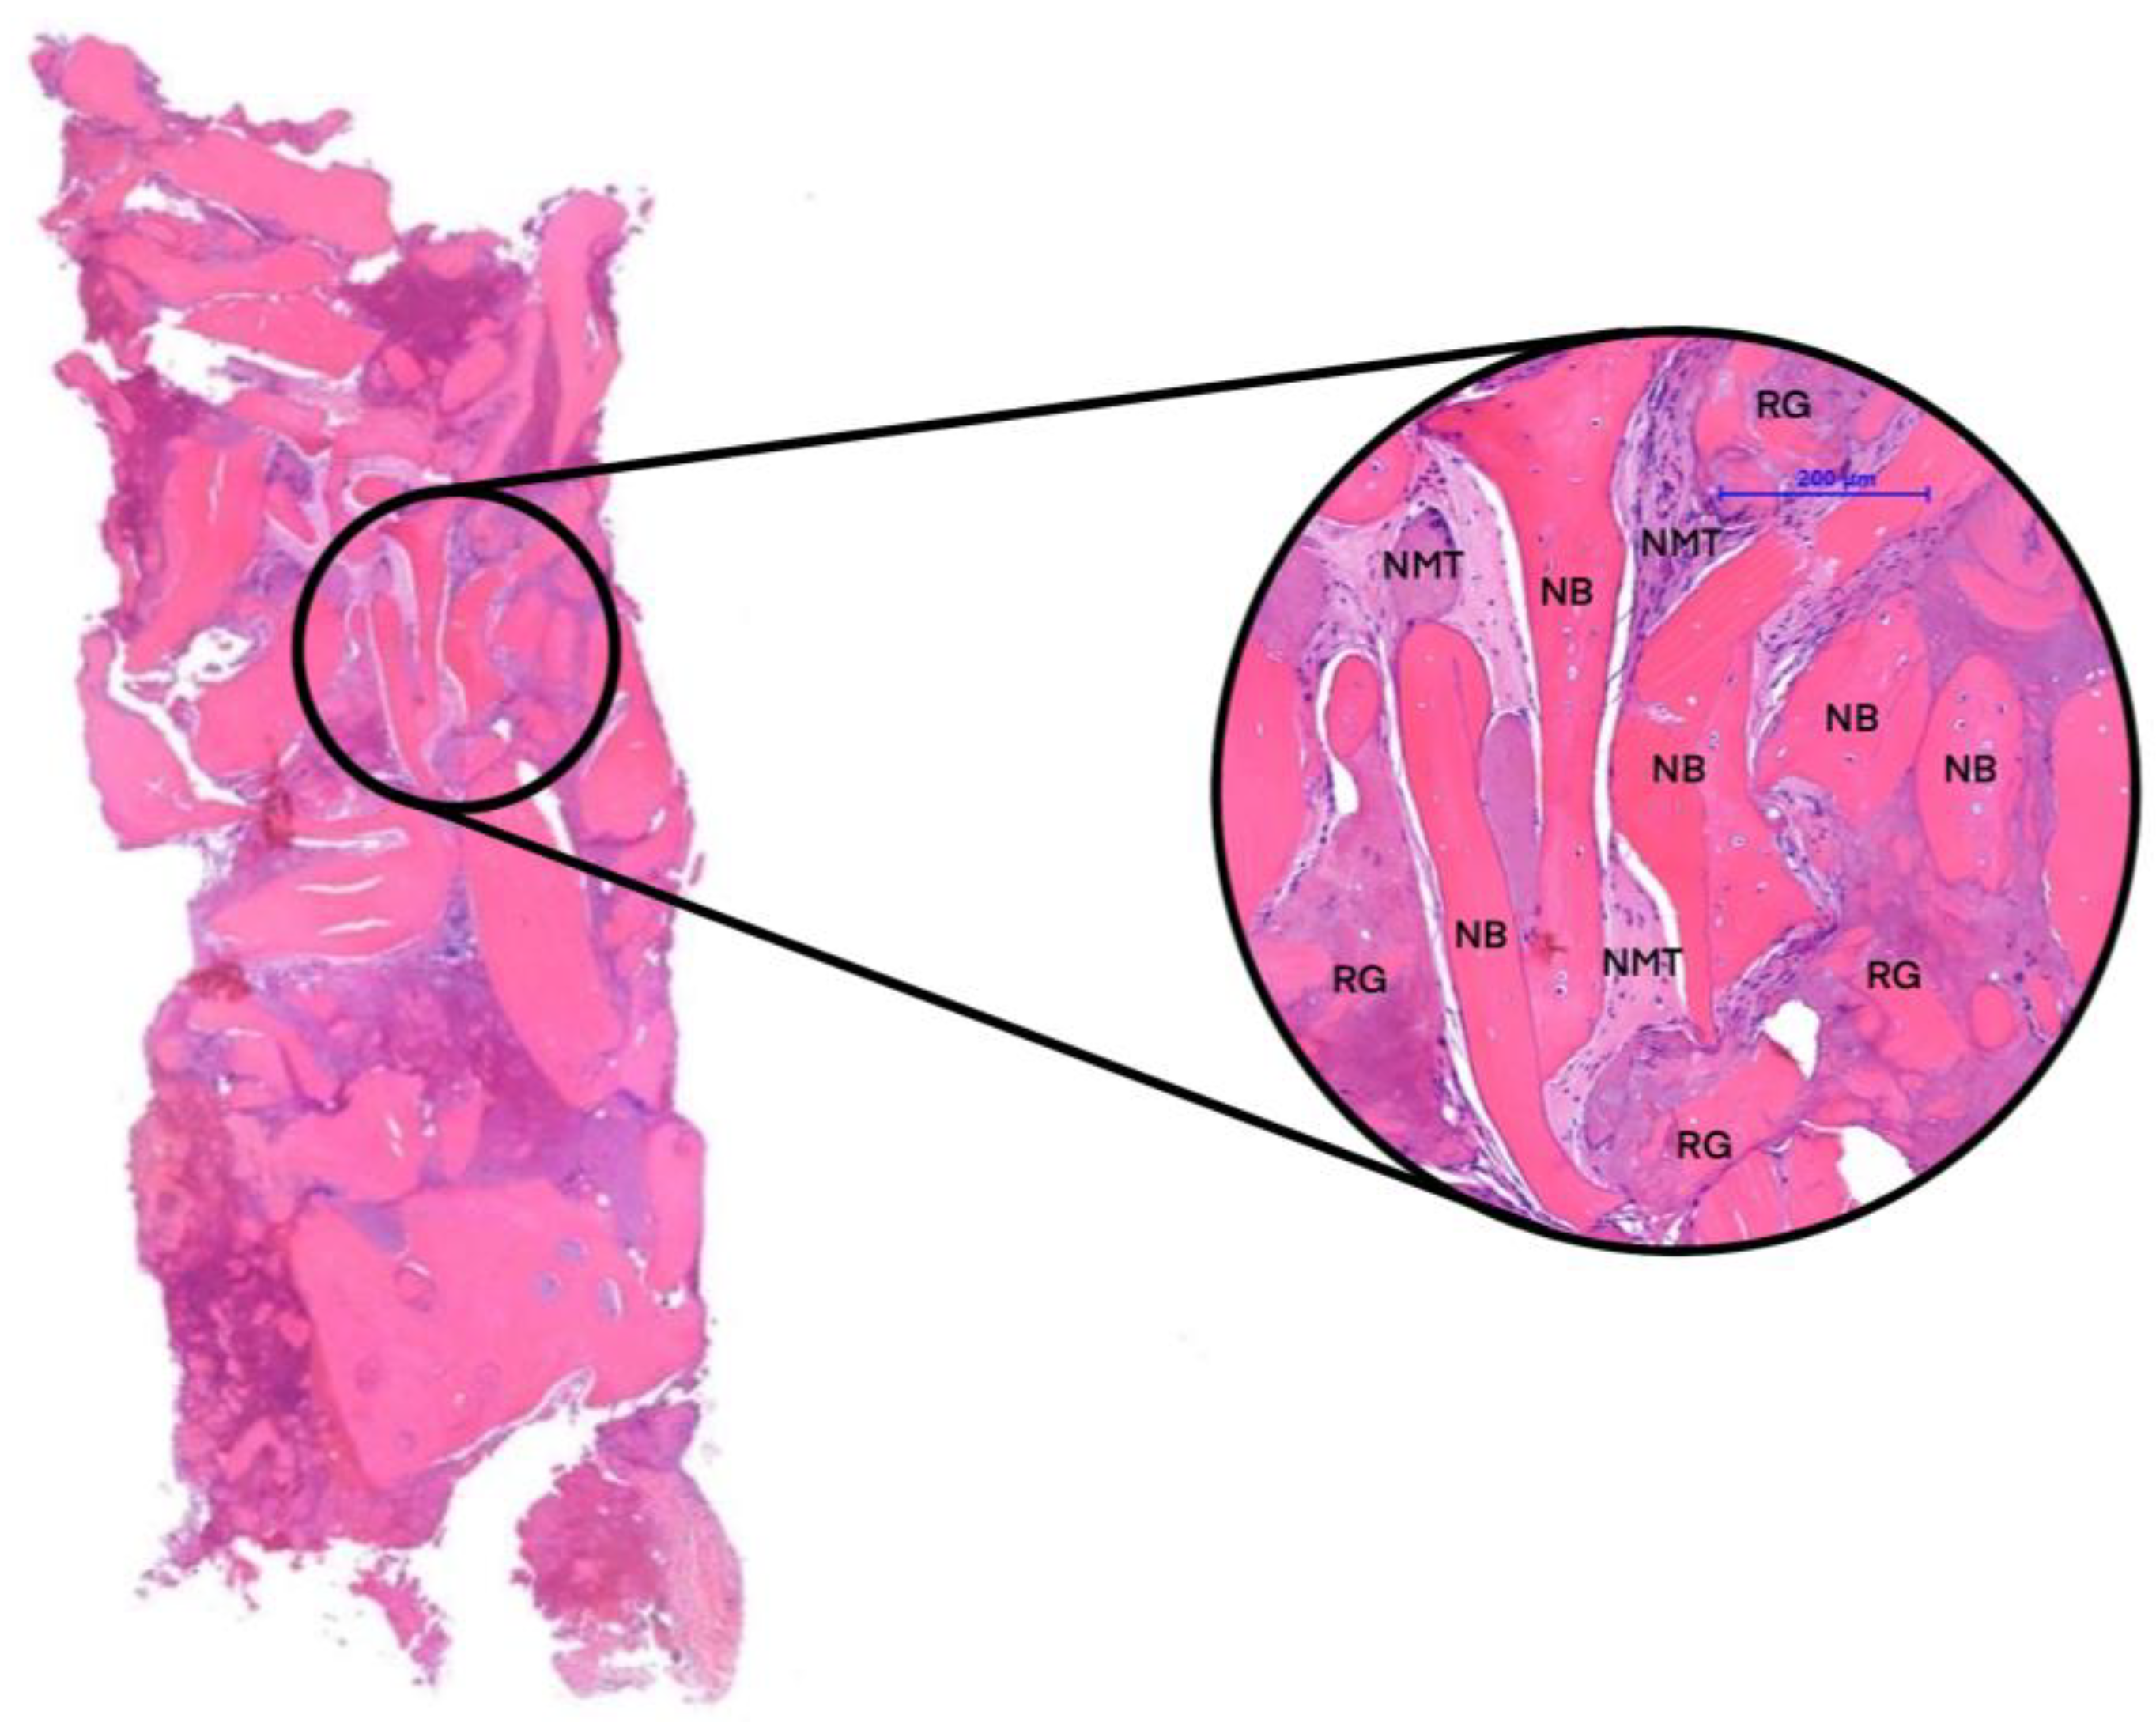

3. Results

| Groups | n | NFB | NMT | RG |

|---|---|---|---|---|

| 3 months of healing | 2 | 40.59% | 30.82% | 28.59% |

| 6 months of healing | 2 | 55.92% | 27.95% | 16.13% |

| Native bone (NB) | 4 | 60.78% | 39.22% | - |